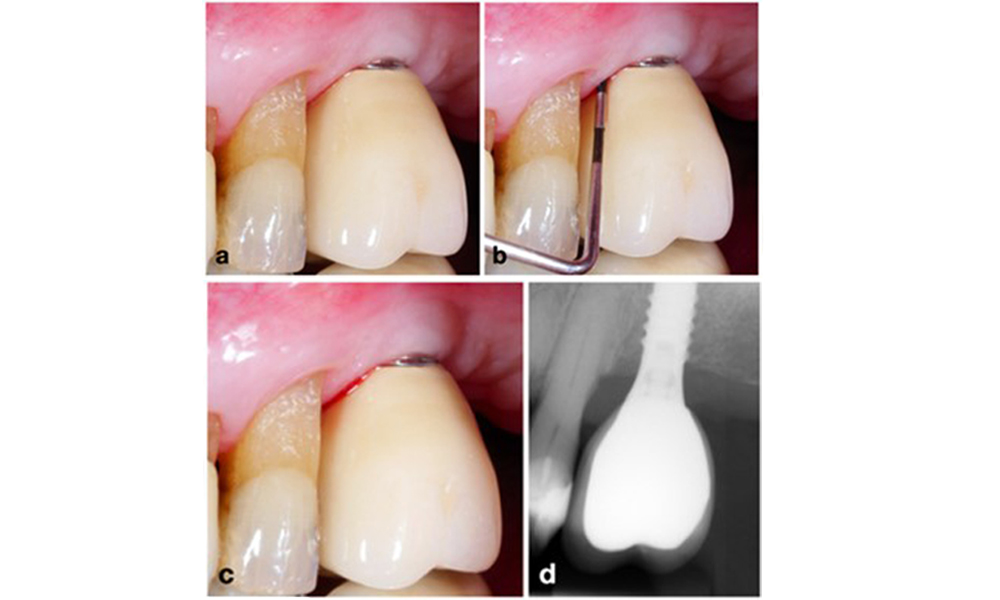

По време на Световния семинар за класификация на пародонталните и периимплантни заболявания и състояния през 2017 г. бяха определени диагностичните критерии за периимплантатен мукозит и периимплантит (Renvert et al. 2018). Периимплантният мукозит се дефинира като (1) наличие на възпаление около импланта (т.е. зачервяване, подуване, линия или капки кръв в рамките на 30 секунди от сондирането), но (2) без допълнителна костна загуба след първоначалното заздравяване (фигура 1 ).